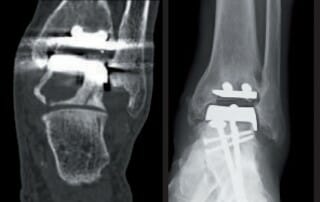

Periprothetische Zysten nach Sprunggelenkendoprothetik

Chirurgische Behandlungsoptionen – Ein Kurzzeit-Follow-up in 17 Fällen Die Autoren stellen in diesem Beitrag unterschiedliche chirurgisch-therapeutische Optionen im Umgang mit großen periprothetischen Zysten (PPZ) nach endoprothetischem Ersatz des oberen Sprunggelenkes [...]